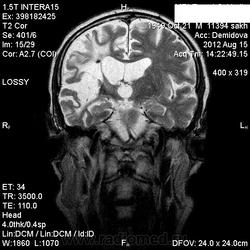

1 случай -локальная гемиатрофия.2 случай-диффузная.

Молодой человек после автомобильной аварии.3 года лежит.Двигаются только глаза.Зрелище душещипательное.

Евгений, конечно же, мои случаи не являются "чистой" атрофией-согласна.Мне пока не встречались случаи болезни Пика, Альцгеймера и другие "чистой воды" атрофии.Второй случай- состояние после длительной комы вследствие автодорожной травмы 3 года назад.Пациент проходил исследование в прошлом году , в этом родители привезли на динамику.